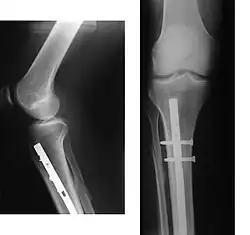

| Internal and external views of an arm with a compound fracture, both before and after surgery | |